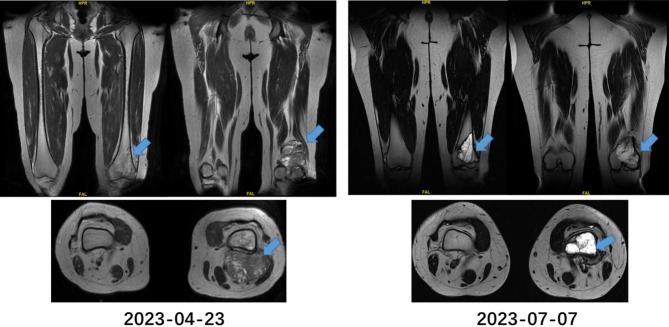

Ewing's sarcoma (ES) is an aggressive small round cell tumor traditionally diagnosed through open biopsy. We present a systematically evaluated case suggesting that standardized ultrasound-guided fine-needle aspiration cytology (FNAC), when combined with immunohistochemical (IHC) and molecular analysis, may provide diagnostic reliability approaching that of open biopsy. A 26-year-old female presented with an insidiously developing left popliteal fossa mass. Ultrasound-guided FNAC demonstrated characteristic small round blue cells, with IHC showing diffuse positivity for CD99, FLI-1, and Bcl-2. Subsequent fluorescence in situ hybridization (FISH) analysis identified the EWSR1 gene rearrangement. The patient exhibited significant radiographic response to neoadjuvant chemotherapy after two cycles, as evidenced by MRI. Definitive surgical resection specimens similarly demonstrated EWSR1 rearrangement by FISH, corroborating the initial diagnosis. Following four adjuvant chemotherapy cycles, the patient achieved disease-free status at the last follow-up. This case highlights the potential utility of optimized FNAC specimen triage (incorporating smears, liquid-based cytology, and cell blocks) for rare tumors, enabling comprehensive ancillary testing while maintaining diagnostic accuracy and supporting timely therapeutic decision-making.